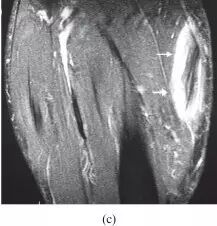

![]()

图26.一名78岁女性的平滑肌肉瘤患者出现右腿疼痛,肿胀和无法行走。 (a)通过小腿的轴向T1加权的MR图像显示在胫骨前部和胫骨后肌中主要为低信号强度的大的、小叶的、清晰分界的团块损伤(箭头)。团块延伸到皮下组织(箭头)。由于身体活动减少,胫骨后隔室中的肌肉显示突出的脂肪浸润(星号)。 (b)具有脂肪抑制的轴向T2加权MR图像显示具有低信号(空心箭头)的外周坏死区域的主要高信号强度(箭头)的肌内病变。在该脂肪抑制图像上,比较在胫骨后部(星号)中的低信号强度,脂肪替代肌肉的外观与部分(a)中的脂肪替代肌肉的外观。 (c)具有脂肪抑制的轴向T1加权MR图像显示包块的不均匀增强(箭头)。包块病变的活组织检查提示胫骨肌肉的平滑肌肉瘤。 T,胫骨。